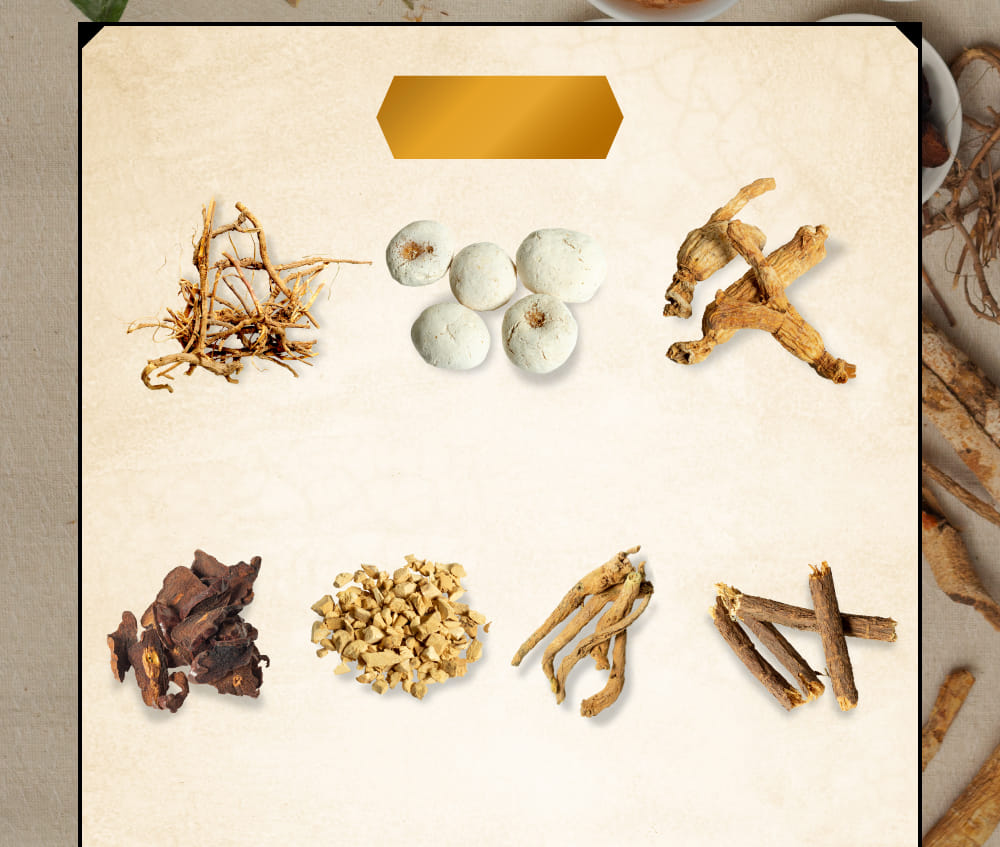

漢方生薬

胆石⋅胆のう炎の疼痛の

炎症緩解に特化した

13種類の

独自配合生薬。

サイコ

セリ科ミシマサイコの根を

乾燥させたもの

効能・効果

消炎・鎮痛作用

ハンゲ

サトイモ科カラスビシャクの

コルク層を

取り除いた

塊茎を乾燥したもの

効能・効果

消化不良改善作用

オウゴン

シソ科のミコガネハナの

根の周皮を除去したもの

効能・効果

解熱・消炎・解毒作用

タイソウ

クロウメモドキ科

のナツメの

成熟した果実を

乾燥させたもの

効能・効果

鎮静・鎮痛作用

ニンジン

オタネニンジンウコギ科の

細根を除いた根を

乾燥したもの

効能・効果

消化促進作用

ショウキョウ

ショウガの根茎を乾燥し、

周皮を除いたもの

効能・効果

抗炎症・消化促進作用

カンゾウ

マメ科カンゾウ属の植物で

根や根茎を乾燥したもの

効能・効果

消化促進作用

3つの生薬

モッコウ

キク科モッコウの根を

乾燥したもの

効能・効果

健胃作用

ソウハクヒ

桑の根の葉をはいだもの

シソシ

シソ科のシソなどの果実を

乾燥したもの